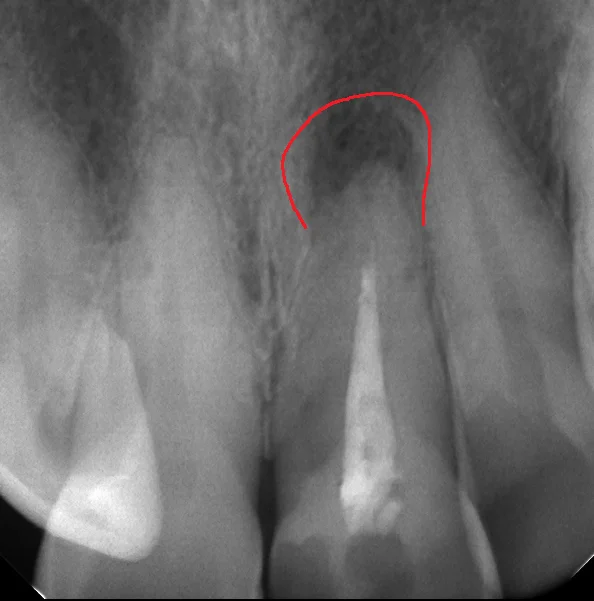

中心結節破折が原因で起こった神経の壊死を放置して、外部吸収が起こったケース

中心結節破折が原因で起こった神経の壊死を放置して、外部吸収が起こったケース